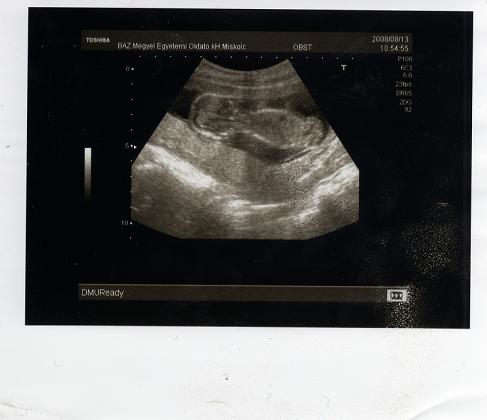

Íme a tegnapi képek.

A kakasos képet úgy képzeljétek el, hogy ülő pózban van a baba és mi alulról látjuk a fenekét. Kép Öcskös